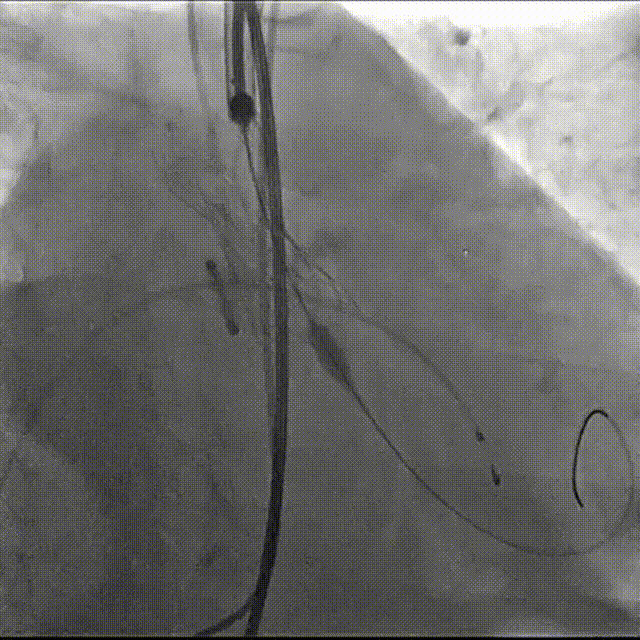

主动脉根部造影

导丝跨瓣

23mm球囊预扩